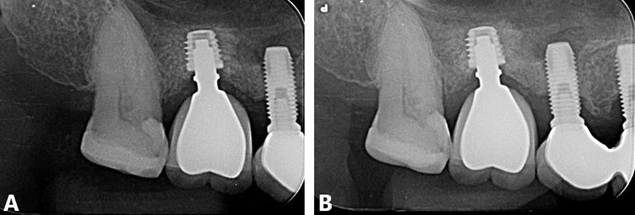

Inicialmente o bloqueio regional foi realizado utilizando anestésico local Alphacaíne 2% Lidocaína com Epinefrina 1:100.000 (DFL, Rio de Janeiro – RJ, Brasil). O procedimento cirúrgico seguiu-se pela incisão da região com lâmina 15, descolamento com instrumental Molt 9 (Quinelato, Rio Claro – SP, Brasil) e fresagem com broca Titamax 2.0 (Neodent, Curitiba – PR, Brasil), seguindo a sequência recomendada pelo fabricante. Após a instalação do implante curto, a sutura foi realizada com fio de nylon 4.0. O paciente foi instruído dos cuidados pós-operatórios, com prescrição medicamentosa de Amoxicilina 500mg de 8/8 horas por 7 dias, Nimesulida 100mg de 12/12 horas por 5 dias e Dipirona sódica 500mg de 4/4 horas por 3 dias. Ausência de complicações pós-operatórias foram evidenciadas (Figura 02. A,B)

Posteriormente, paciente foi reabilitado com prótese unitária sobre implantes (Figura 02. C,D) e o acompanhamento clínico e radiográfico (Figura 03. A, B) está sendo realizado até o presente momento, evidenciado resultado estável.

Figura 02. A, B) Etapa operatória da instalação do implante dental curto. C, D) Tratamento finalizado. Aspecto final com a reabilitação protética-implante.

Figura 03. A, B) Radiografias periapicais final.